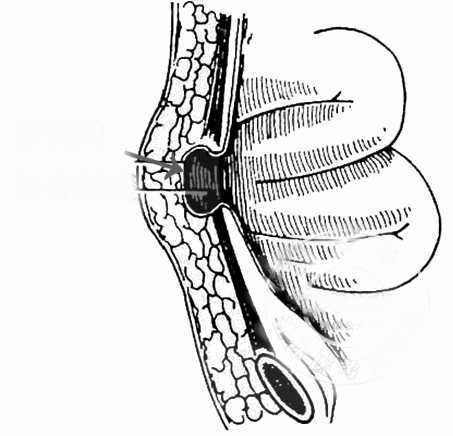

70多岁的王女士来到医院就诊,刚开口说话,立马脸就红了。她说肚脐发炎了,流出的东西跟大便一样,觉得很脏,一直羞于看医生,最近感觉症状越来越严重,还出现了肚子痛,这才来到医院就诊。 通过检查,我发现王女士的肚脐上有一个洞,周围红肿,一碰就痛;挤压肚脐,周围会流出像大便一样的东西。我拿着棉签探了探,发现里面很深,已经进入腹腔。 直觉告诉我,这不是单纯的脐炎,一定另有“玄机”。 通过进一步了解,我得知,几十年前,王女士这里曾经有一个包块,因为不痛不痒,包块也能下去,一直也没治疗;最近一段时间,这个包块变大了,变硬了,隐隐还出现了疼痛,并且破溃了,开始流出来的是带有臭味的脓液,换了几次药不见好转,最后流出来的就是像大便一样的东西。 多年的经验告诉我,这应该是一个特殊的脐疝——Richter疝(一种特殊的嵌顿疝),疝出来的只是一部分肠管,卡住之后出现慢性缺血和坏死,最后穿孔、破溃,导致大便从肚脐里流出来。王女士的CT检查结果证实了我的判断:横结肠的一部分肠壁从肚脐疝出来了,穿孔之后形成了肠瘘,因为大部分的肠管还是通畅的,所以并没有形成肠梗阻。王女士出现的疼痛,则是脐疝周围的感染引起的。 真相终于大白。接下来,我们为王女士实施了腹腔镜下的微创手术:切除了肠瘘,修补了脐疝。 术后没几天,王女士就康复了,很快出院。 我在这里提醒大家,Richter疝是一种特殊类型的疝,指的是肠壁的一部分进入疝囊,而肠系膜侧肠壁及系膜不进入疝囊,多由慢性腹腔压力增加而引起,较高的腹腔内压力使得腹膜被推挤进入人体先天性薄弱区域,从而形成疝囊。由于疝环狭小,疝囊浅,当肠管疝入时只有肠壁的一部分成为疝内容物,而肠系膜侧肠壁没有进入疝囊;同时,由于周围组织弹性差,肠壁一旦疝入很难自行复位,常常造成肠壁的嵌顿,使患者出现腹痛、呕吐等症状,严重时甚至出现坏死及穿孔。通过彩超或者CT检查往往可以明确诊断,而手术则是唯一可以治愈的方法。 (作者供职于郑州市中心医院)